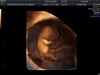

Ja wczoraj o 14 stej miałam spotkanie z maleństwem 3 cm i serduszko bije na 169. Ale dopadła mnie infekcja szyjki w cytologii wyszło i teraz na globulkach lecę i się zamartwiam bo to dopiero 10 tydzień skończony. Zdjęcie mało widoczne ale jest .Zobacz załącznik 1014892

Pochwalę się jeszcze raz ! :) ale nie umiem filmików dodać jak rusza odnóżami haha:D

Załączniki

• Bez tytułudf.jpg

Bez tytułudf.jpg

79,6 KB · Wyświetleń: 120

• IMG_20190826_1_6dd.jpg

IMG_20190826_1_6dd.jpg

63 KB · Wyświetleń: 122